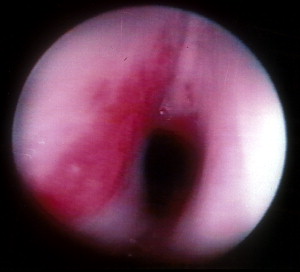

Microlaryngoscopy is performed with a rigid anterior commissure-type laryngoscope such as a Benjamin or Parsons placed in the vallecula ( Fig. 2 ) and used to expose the endolarynx and subglottic airway. This will reveal a subglottic hemangioma just below the vocal cords ( Fig. 3 ). Magnification from a Storz Hopkins telescope is used to visualize the subglottic airway and the scope can be passed down to the level of the carina. It is important to carefully look at the trachealis muscle in the back wall of the trachea for staining, fullness, and signs of vascular disease ( Fig. 4 ). Tracheal hemangioma may be subtle and its treatment is challenging.